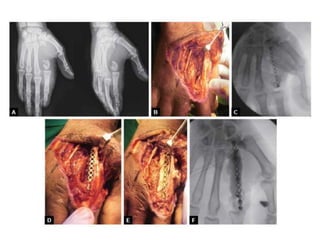

Principles of surgical treatment

• Bone and soft tissue debridement.

• Removal of foreign body

• Stabilization of the bone

• Local antibiotic therapy

• Dead space management

• Reconstruction of the soft tissues

• Reconstruction of the osseous defect.